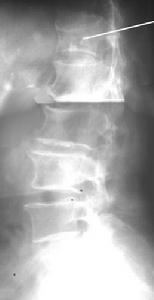

檢查1.X線檢查 除顯示脊柱有不同程度的增生及退變外於正位片上可發現椎板間隙消失或模糊不清密度增高;側位片顯示基底位於椎板及關節突的骨化塊突向椎管方向因椎弓根的遮擋僅在椎間孔投影處顯示指向椎間隙的高密度陰影骨化灶以中下胸椎為多見,病變範圍以多節段為多(4~5節段),亦有單發或長達8個節段者。從骨化的形態來看約50%的病例為鳥嘴型最為多見,其次為線型結節型和鉤狀型。

4.MRI檢查 主要用於觀察骨化的黃韌帶與脊髓的關係一般列為常規檢查尤其是擬行手術的病例(圖1)。